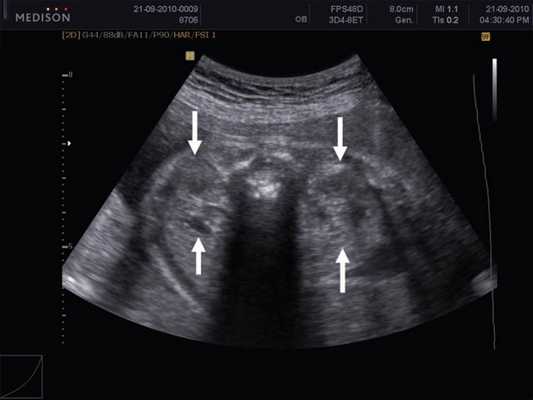

Надпочечники с обеих сторон были интактны. Мочевой пузырь был увеличен до 20 мм в диаметре, с утолщенными стенками и в процессе динамического осмотра не опорожнялся (рис. 5). Изменений по остальным органам и системам не было выявлено.

Рис. 5. Расширенный мочевой пузырь плода.

Ультразвуковые изменения правой почки были более выраженными. По заднему краю образования диаметром 36 мм была распластана сама почка. Мочеточники с обеих сторон не визуализировались ни на одном из своих участков вплоть до места впадения в мочевой пузырь. Нормальное количество околоплодных вод, мужской пол плода, отсутствие расширенных мочеточников на фоне относительно небольшого увеличения размеров мочевого пузыря позволили нам исключить атрезию уретры, синдром задних уретральных клапанов и мегацистис-микроколон-интестинальный гипоперистальтический синдром и предположить наличие обструктивного поражения мочевыводящих путей на высоком уровне.